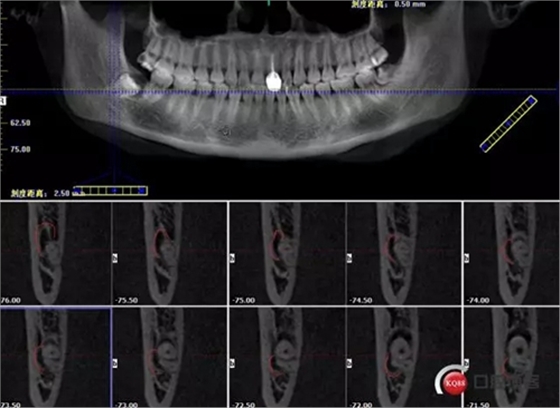

牙齒下1/3神經(jīng)管在頰側(cè)